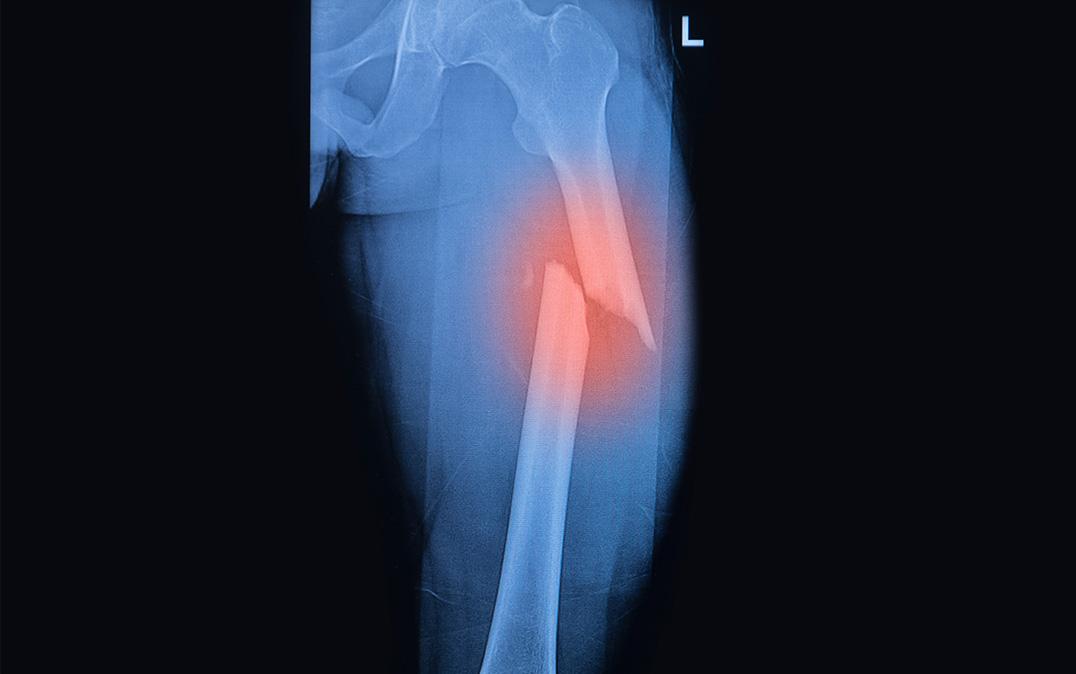

Stem Cell Population Identified That Is Key for Bone Regeneration

image picture Image by Praisaeng/Shutterstock

Researchers from the University of Tsukuba, in collaboration with the University of Bonn, Germany, identify a subpopulation of mesenchymal stem cells with enhanced fracture healing and differentiation abilities

Tsukuba, Japan—Mesenchymal stem cells (MSCs) are thought to have great potential in the field of regenerative medicine, which has the aim of restoring damaged tissues. However, not much was known about in vivo plasticity of them—until now. Researchers have identified a subpopulation of MSCs that promote the healing of bone fractures and show an enhanced ability to differentiate into various cell types.